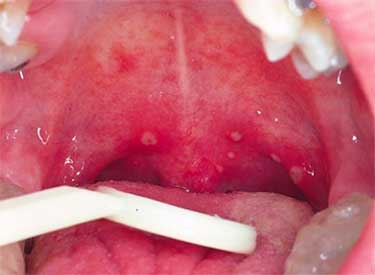

При огляді глотки визначають почервоніння або яскраво-рожевий колір її тканин, виражену набряклість. Провідним симптомом хвороби є висип на запалених тканинах, за зовнішніми характеристиками нагадує герпетичні висипання.

Основне місце скупчення висипу – область мигдалин і навколишні тканини. Але патологічний процес може поширюватися на небо, а у важких випадках і на всю ротову порожнину. Оскільки висип нагадує прояви герпесу, це послужило приводом для присвоєння назви хвороби на домикроскопическом етапі розвитку медицини.

На поверхні слизової задньої стінки глотки на тлі запалення і почервоніння можна виявити дрібні бульбашки. Вони можуть покривати практично всю поверхню мигдалин. Якщо доторкнутися до них ложкою, оболонка швидко розривається і випливає кровянистое вміст.

Запалення глотки при герпесной ангіні зберігається протягом 6-7 днів. Через 5-6 днів бульбашки починають лопатися, і мигдалини покриваються численними ерозіями і виразками. При будь-якому дотику вони починають кровоточити.

При герпетичної ангіни в горлі помітна своєрідна висип – червоні пухирці на задній стінці горла, язику, піднебінні і мигдалинах. Характерно, що малюки до 4 років скаржаться не стільки на горлову біль, скільки на біль у животі та нудоту.

При герпетичної ангіни у дітей швидко наростають місцеві зміни. Вже в перші дві доби на тлі гиперемированной слизової мигдаликів, піднебінних дужок, язичка, піднебіння в ротовій порожнині виявляються дрібні папули, які швидко перетворюються у везикули діаметром до 5 мм, заповнені серозним вмістом. Через 1-2 дні пухирці розкриваються і на їх місці утворюються білувато-сірі виразки, оточені вінчиком гіперемії. Іноді виразки об’єднуються, перетворюючись у поверхневі зливні дефекти. Утворюються ерозії слизової різко болючі, у зв’язку з чим діти відмовляються від їжі і пиття. При герпетичної ангіни у дітей виявляється двостороння подчелюстная, шийна і привушна лімфаденопатія.

У даному прикладі ми розглянемо відмінності фолікулярної ангіни від герпетичної. На фото під № 3 показана герпангіна, а на фото під № 4 гнійна ангіна. Відмінності очевидні, при гнійній ангіні уражаються тільки мигдалини, до того ж гнійні виділення на мигдалинах несхожі на бульбашкові висипання при герпетичної ангіни.